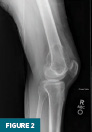

Anteroposterior and lateral radiographs of the right knee demonstrated an expansile lesion involving the lateral aspect of the distal femur. The lesion was primarily lucent and had a relatively narrow zone of transition (Figures 1 and 2). Soft tissue density involving the superior aspect of the lesion was suggestive of cortical breakthrough (Figure 1).

Radiographs, CT, and MRI all contribute to establishing the diagnosis. Radiographically, GCTB lesions are typically lytic and eccentric, arising in the metaphysis of long bones and extending into the epiphysis, often to the subarticular bone. Most lesions are geographic with a narrow transition zone. A sclerotic margin is usually absent, although up to 5% of cases demonstrate sclerosis. CT is useful for evaluating cortical thinning and breakthrough, as illustrated in this case. On MRI, lesions typically demonstrate low to intermediate signal intensity on T1-weighted images and demonstrate inhomogeneous signal intensity on T2/STIR sequences, due to hemorrhage or collagen content. Postcontrast images reveal heterogeneous enhancement. These features were evident in our patient’s imaging and were central to guiding the diagnosis.